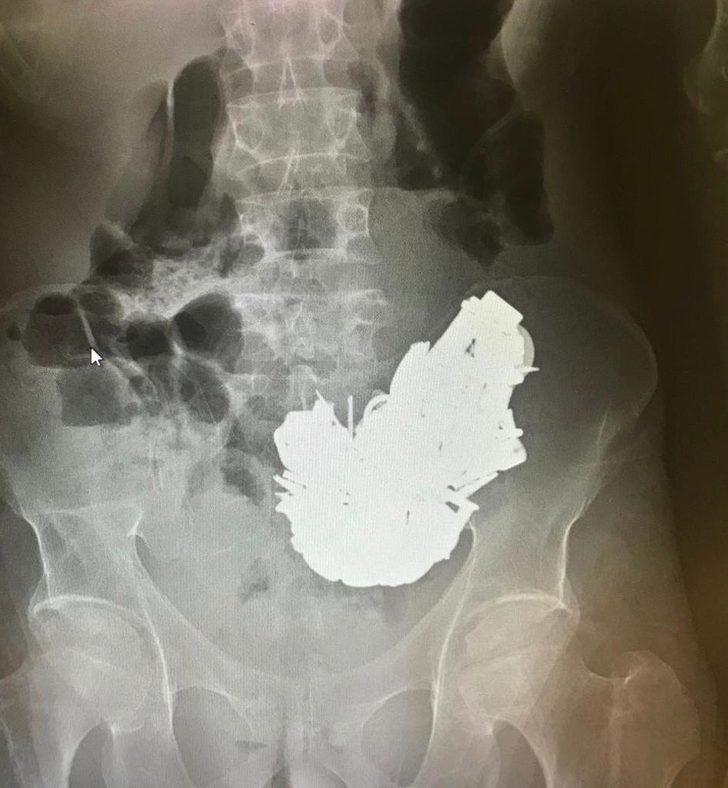

Edinilen bilgiye göre, herkesi hayrete düşüren olay, Bornova ilçesinde yaşandı. İlçede ikamet eden E.D. (41) isimli bir adam, karın ağrısı şikayetiyle Ege Üniversitesi Tıp Fakültesi Hastanesi'ne ailesi tarafından kaldırıldı. E.D.’nin röntgen filmini çeken doktorlar, şahsın midesinde 200’e yakın 680 gram ağırlığında metal parça bulunduğunu tespit etti. Durumu kötüleşen hasta acil olarak ameliyata alındı.

Hastanın karnında tespit edilen metal cisimler yaklaşık 3 saat süren bir operasyonla alındı. Ameliyatın ardından yoğun bakım servisine kaldırılan hasta, yaşadığı zehirlenmenin etkisiyle hayatını kaybetti.

Ege Üniversitesi Tıp Fakültesi Hastanesi Başhekimi Prof. Dr. Tuncay Göksel, hasta hakkında yaptığı açıklamada, "Psikiyatrik rahatsızlığı olan bir hastamızdı. Bir takım rahatsızlıkları nedeniyle; metaller, mıknatıslar yutmuş. Hastanın midesinden yaklaşık 680 gram metal çıkarıldı. Başarılı bir operasyon gerçekleştirdik; fakat bu metallerin midede durması uzun süre içersinde metal zehirlenmesine yol açtı. Buna bağlı bütün kan değerlerinde çok hızlı düşüş oldu. Bu metallerin oluşturduğu toksik zehirlenmeden dolayı bugün hastayı kaybettik” açıklamasında bulundu.